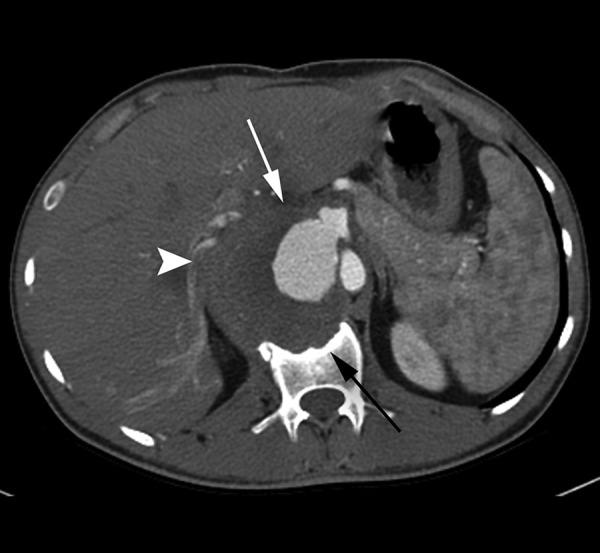

A 22-year-old man, who had undergone gastric, pancreatic and aortic surgery 2.5 years earlier, presented with progressive abdominal pain. Multidetector computed tomography scan revealed an 8-cm celiac pseudoaneurysm. We report a giant celiac pseudoaneurysm treated with stent-graft implantation.